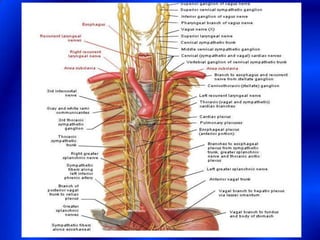

This document provides information about a barium swallow procedure. It begins with an introduction and overview of the embryology and anatomy of the pharynx and esophagus. It then describes the procedure itself, including preparation, technique, views obtained, and indications. Specific conditions that may be examined include pharyngeal and esophageal webs, foreign body impaction, scleroderma, dysphagia, mediastinal masses, and carcinoma. Diagrams are provided to illustrate normal anatomy and various pathological findings.